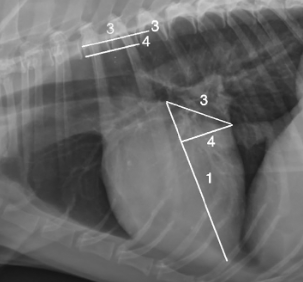

이런것도 있다.

여러가지 선들을 그어가면서 새로운 지표들이 부지불식간에 쏟아져 나오고 있다는 것은 알고 있어야 한다.